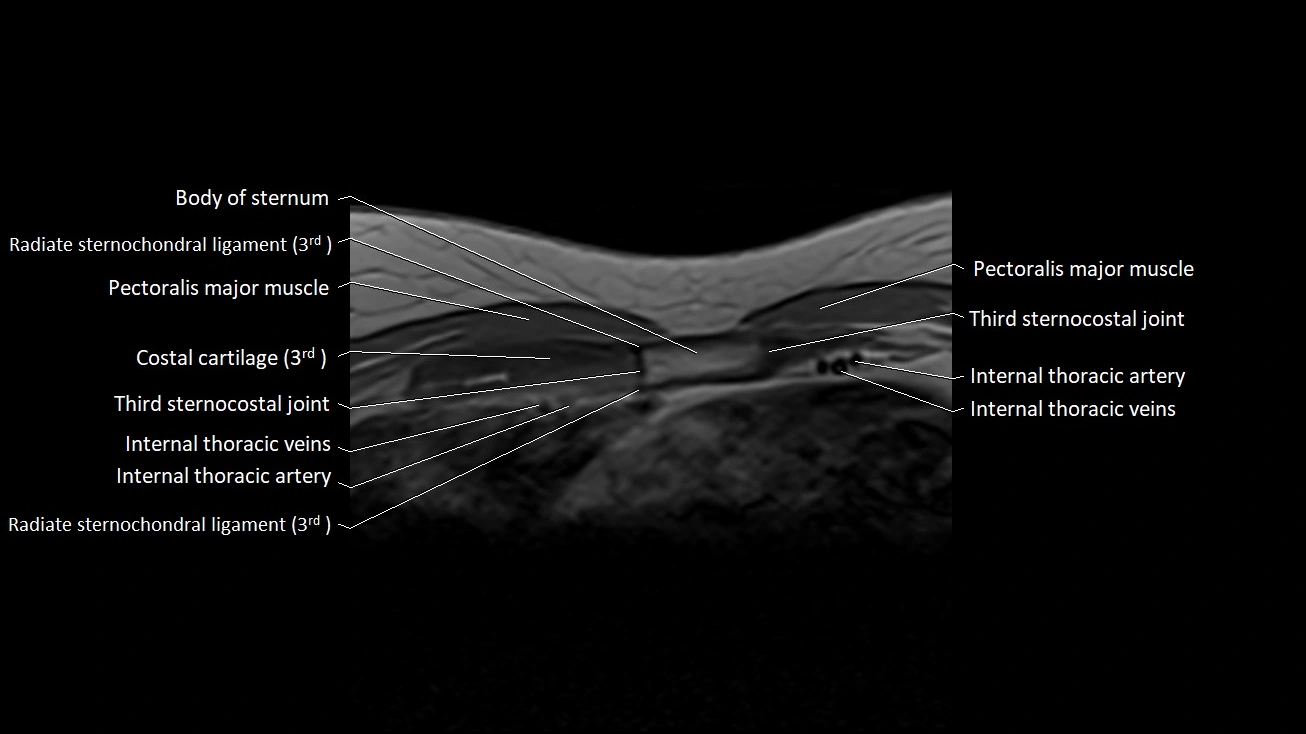

MRI images

image